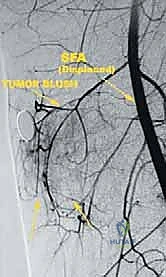

Based on our imaging, we classify these tumors into three types, which dictates our resection strategy:

* Type 1 (Luminal) Tumors: These arise from within the sartorial canal space itself, typically from fat or fibrous tissue. They lie "loose" within the space, approximating but not adherent to the vessel walls or surrounding muscles.

FIG 3 • Type 1 (luminal) tumors lie within the space and are resected with a thin cuff of tissue that surrounds them.

* Type 2 (Wall) Tumors: These originate from one of the muscular walls bordering the canal (sartorius, vastus medialis, adductor magnus, or adductor longus). They arise from within the muscle or its fascia.

FIG 3 • Type 2 (wall) tumors arise from the muscles surrounding the space and are resected as a typical muscle resection.

* Type 3 (Vessel) Tumors: These are the most challenging, as they directly involve arteries, veins, or nerves. They originate from, or have directly invaded, the vessel wall, not simply juxtaposed to it.

FIG 3 • Type 3 (vessel) tumors invade the vessels and are therefore resected en bloc with the vessels.

This classification helps us predict the difficulty of resection and reconstruction, and critically, the necessary surgical margins.